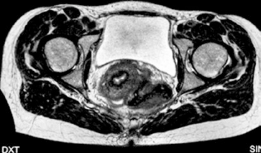

التصوير المقطعي والرنين المغناطيسي

بالإضافة إلى الأشعة السينية، تُستخدم تقنيات تصوير أكثر تقدماً لتوفير تفاصيل أدق حول المفصل:

التصوير المقطعي المحوسب (CT) مع إعادة البناء ثلاثي الأبعاد (3D Reconstruction): يوفر معلومات لا تقدر بثمن حول مورفولوجيا (شكل) التجويف الحُقي، وكروية رأس الفخذ، ووجود أي نتوءات عظمية (Osteophytes). يسمح التخطيط ثلاثي الأبعاد بالتخطيط الدقيق لقطع العظم المتوقعة وزاوية دوران جزء الحُق، وهو مفيد بشكل خاص في حالات خلل التنسج الثنائي لتخطيط الإجراءات المرحلية.

التصوير بالرنين المغناطيسي (MRI) / تصوير مفصل الورك بالرنين المغناطيسي (MR Arthrography): يوضح سلامة الشفا الحُقي، وحالة الغضروف المفصلي، ويمكن أن يحدد أي أمراض أخرى داخل المفصل مثل الأجسام الحرة أو تمزقات الرباط المدور، مما يساعد في توجيه الإجراءات التنظيرية المصاحبة. هذه التقنيات ضرورية لتقييم الأنسجة الرخوة التي لا تظهر بوضوح في الأشعة السينية أو الأشعة المقطعية.

يُعد التخطيط الدقيق قبل الجراحة أمراً بالغ الأهمية لتحقيق أفضل النتائج وتقليل المضاعفات. باستخدام برامج القوالب الرقمية، يمكن للجراحين محاكاة إعادة توجيه التجويف الحُقي، وتحديد الاتجاه الأمثل للدوران والترجمة المطلوبة لتحقيق التغطية المطلوبة وتقليل الانحشار. يساعد هذا في التنبؤ بطول المسمار اللازم ومساره للتثبيت. كما أن مراعاة إزاحة رأس الفخذ-العنق مهمة أيضاً لمعالجة أي انحشار فخذي حُقي (Femoroacetabular Impingement - FAI) متزامن.